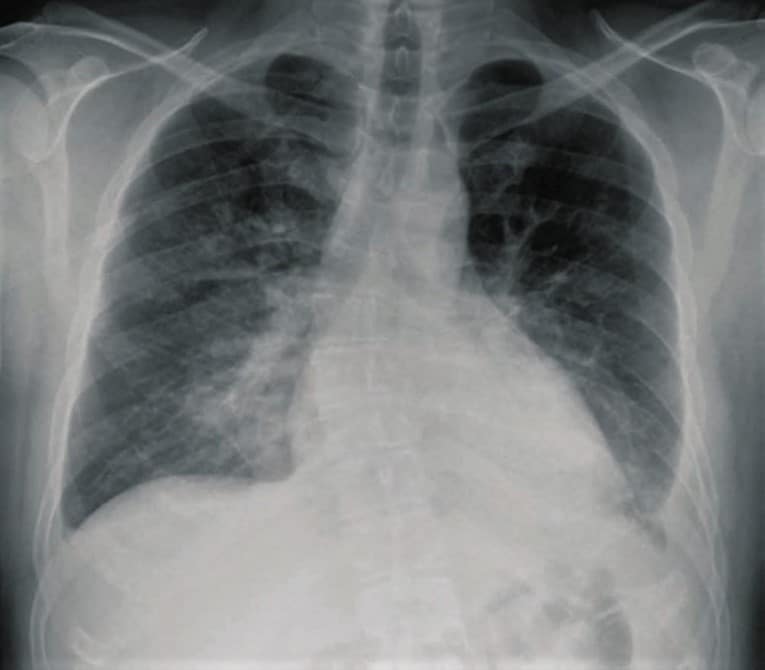

Measles patient with a complication of respiratory failure

Infants, pregnant women, and malnourished children with impaired immune systems are most likely to have complications from measles. The most frequent complication is pneumonia, which can be brought on by a subsequent bacterial infection or the measles virus (Hecht giant cell pneumonia).

Croup, otitis media, and diarrhea from secondary infections are some additional complications. Measles keratoconjunctivitis, which can result in blindness, most frequently affects young children with vitamin A deficiency.